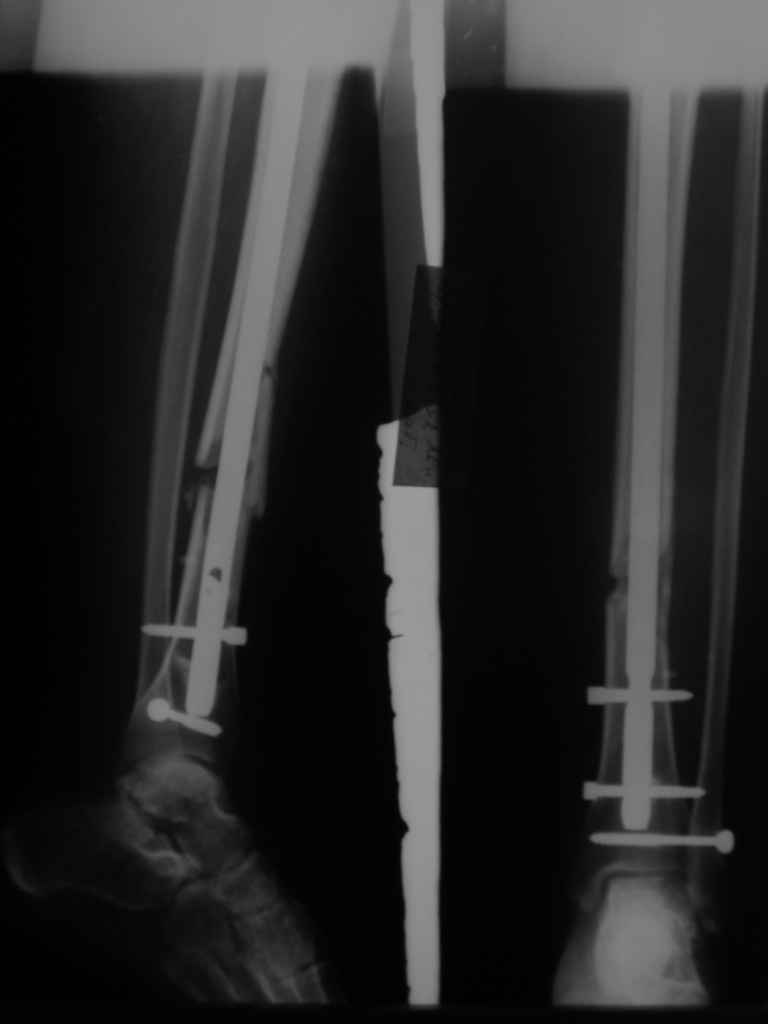

В приложении картинка пациента со сломанным внизу гвоздем. Начал лечение в другом учреждении. Еще и адвокат к тому же.

Динамизировали через 8 недель, а оно поползло больше, чем хотелось бы.

Посмотрев на клинический случай с винтообразным переломом ББ и МБ костей, возник вопрос о целесообразности динамизации фиксатора при подобном типе перлома.

Винтообразный перелом создает обширную зону межфрагментарного контакта, что является благоприятным условием для консолидации, если в ожидаемые 8-10 недель мозолеообразования не наблюдается, то динамизация приводит к *соскальзыванию* проксимального фрагмента- вторичному смещению, величина которого и определяется размером овального окна гвоздя.

Логичным, на мой взгляд, в подобной ситуации является не динамизация гвоздя, а смена гвоздя на больший размер с рассверливанием.

Динамизация скорее показана при поперечных/ short oblique типах, когда зона межфрагментарного контакта ограничена, нет риска вторичного смещения отломков.